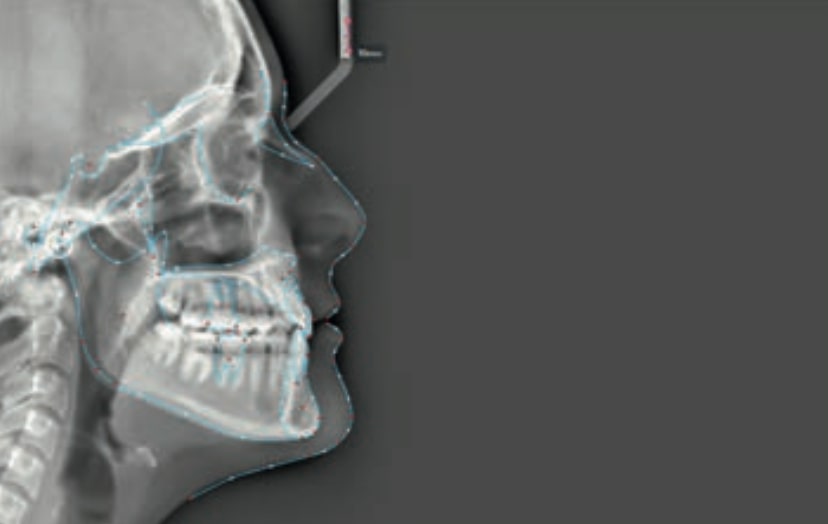

Chief complaint: The patient, a 19-year-old woman, was evaluated to undergo orthodontic treatment using the Angel Aligner Pro system. She presents with a skeletal Class III, mesofacial, with a dental Class III malocclusion and a 2 mm deviation of the lower midline to the left. Teeth 33 and 43 are out of the arch and cortical bone, with a crossbite issue on tooth 33. Fortunately, no functional issues affecting swallowing or breathing have been detected. The patient’s motivation for starting treatment was a general review of her dental and aesthetic health. The soft tissue analysis reveals mandibular protrusion that influences her facial profile. This diagnosis highlights the need for a comprehensive approach to address dental and skeletal misalignments, improving both the patient’s functionality and facial aesthetics.

• Skeletal class III

• Soft Tissue Analysis: Jaw protrusion

Treatment plan